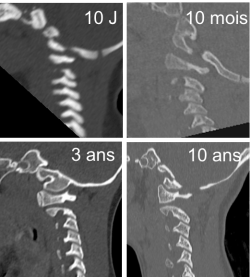

plus que l’os sous chondral, qui est parsemé de vaisseaux nourrissant l’os en croissance en dessous du cartilage de croissance. on rencontre donc des fracture sous-chondrales, une forme de fracture très instable associée à une rupture de tous les ligaments.